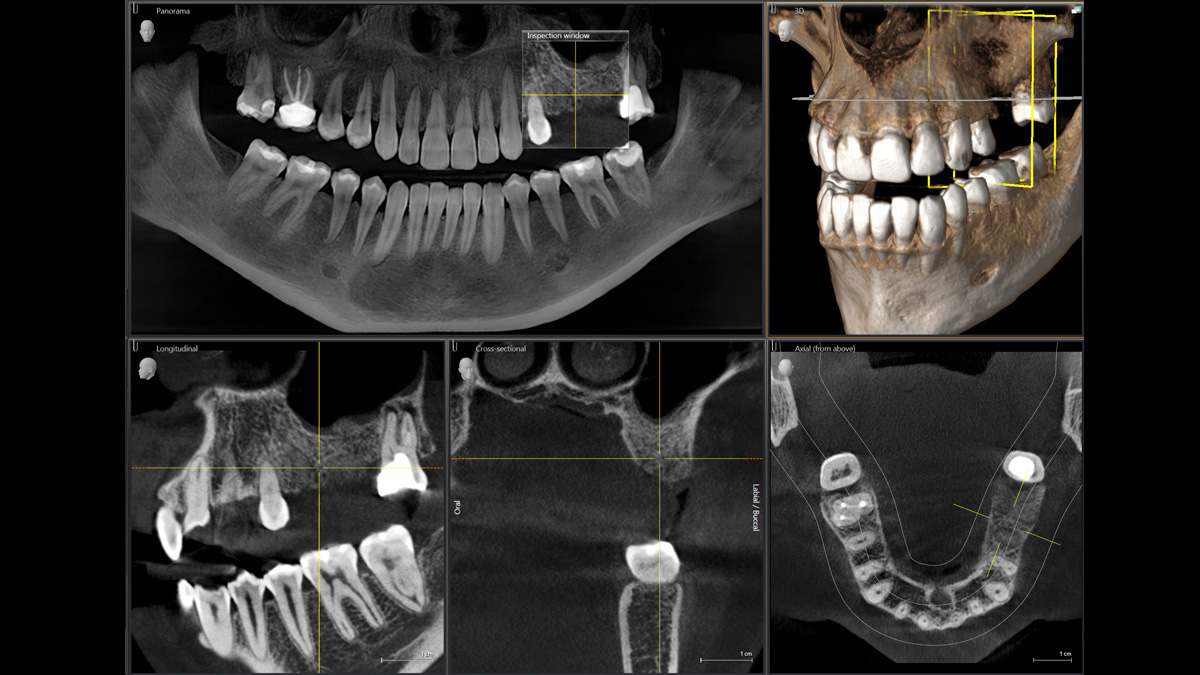

With the 3D Intelligent Low Dose mode, you get 3D images in the dose range of a 2D X-ray. In HD mode (up to 1,400) individual images are captured during a single rotation and converted into a 3D volume with up to 80 μm for low-noise images in high resolution.

A broad range of volume sizes to support your various diagnostic and clinical needs from Ø 5 x 5.5 cm to Ø 11 x 10 cm